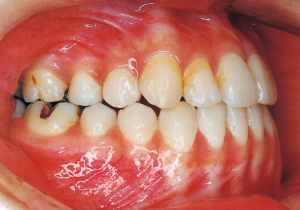

2 After Phase 2 Treatment 5-9-’92

This case presented with Class III malocclusion and significant negative overjet from the early mixed dentition. Regular observation was conducted, and Phase I treatment was initiated after the eruption of the anterior teeth, improving the anterior occlusal relationship and molar relationship. Subsequently, regular observation continued toward the completion of the permanent dentition. However, due to vigorous mandibular growth, orthodontic treatment including surgery became necessary.

16 5-9-’92 After Phase 2 Treatment

Afterwards, follow-up was conducted, but based on the growth pattern, surgical intervention was determined necessary, and the patient entered a period of regular observation.

Post-surgical orthodontic period: 10 months

Retention period: 2 years 5 months